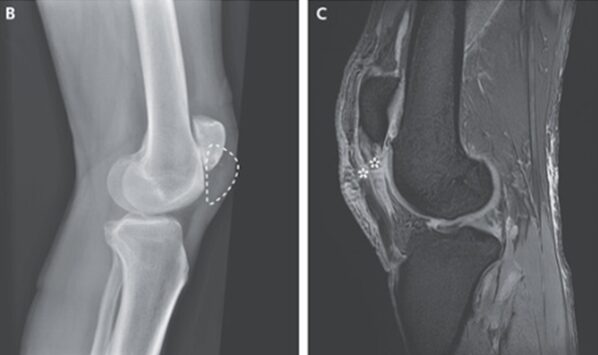

X線では骨折は確認できなかったが、膝蓋骨が正常位置になく高位変位していることが確認された。

MRIでは左膝のT2強調像にて膝蓋骨腱の不連続性が確認された(*印)。